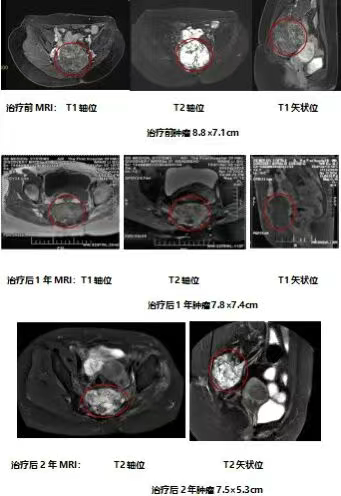

患者周先生,44岁,诊断为骶尾部巨大脊索瘤(约12.5cm×8.9cm×8.1cm),肿瘤与直肠界限不清。通过“外科隔离下根治性重离子治疗”,在手术置入隔离材料后,对紧贴直肠的病灶安全给予根治性剂量,最终肿瘤总剂量达70.4 Gy(RBE),实现肿瘤显著控制,且未出现严重直肠放射性损伤。